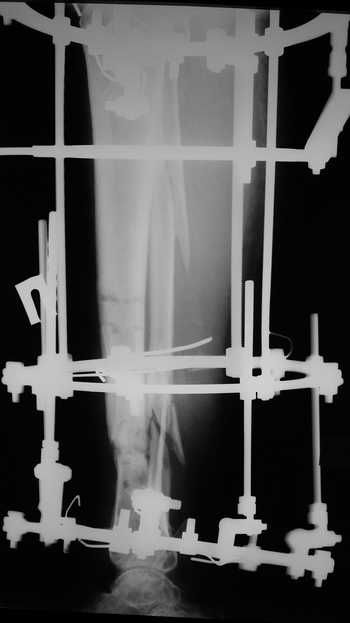

Мужчина, 33 года, резекция б\б кости по поводу остеомиелита после открытого перелома. Стандартная методика билокального остеосинтеза (рис 1 и 2). В конце удлинения выявилось неудовлетворительное взиморасположение перемещенного фрагмента и дистального отломка (рис 3). Планирование (рис 4).

Адаптация отломков гексаподом за 5 дней (рис 5). Замена гексапода на обычные штанги (рис 6 и 7)

Женщина 46 лет, неудачно лечившаяся по поводу перелома голени в нижней 1\3 сначала в гипсе, поступила через 6 месяцев после остеосинтеза пластиной (рис 1). Имелась деформация в нижней 1\3 голени: варус, антекурвация, наружная ротация, два свища. Удалена пластина, дебридмент мягких тканей,

остеотомия м\б кости, аппарат Илизарова. По рентгенограммам в двух проекциях произведено планирование устранения смещений (рис 2 и 3), между вторым и третьим кольцом установлены 6 телескопических дистракторов Гесапода, данные введены в программу, и далее втечение 10 дней больная подкручивала телескопы согласно выданной компьютером инструкции. По завершению репозиции гексаподные телескопы обратно заменены на обычные штанги от аппарата Илизарова (рис 4 и 5). Еще через две недели забит гвоздь (рис 6, контроль